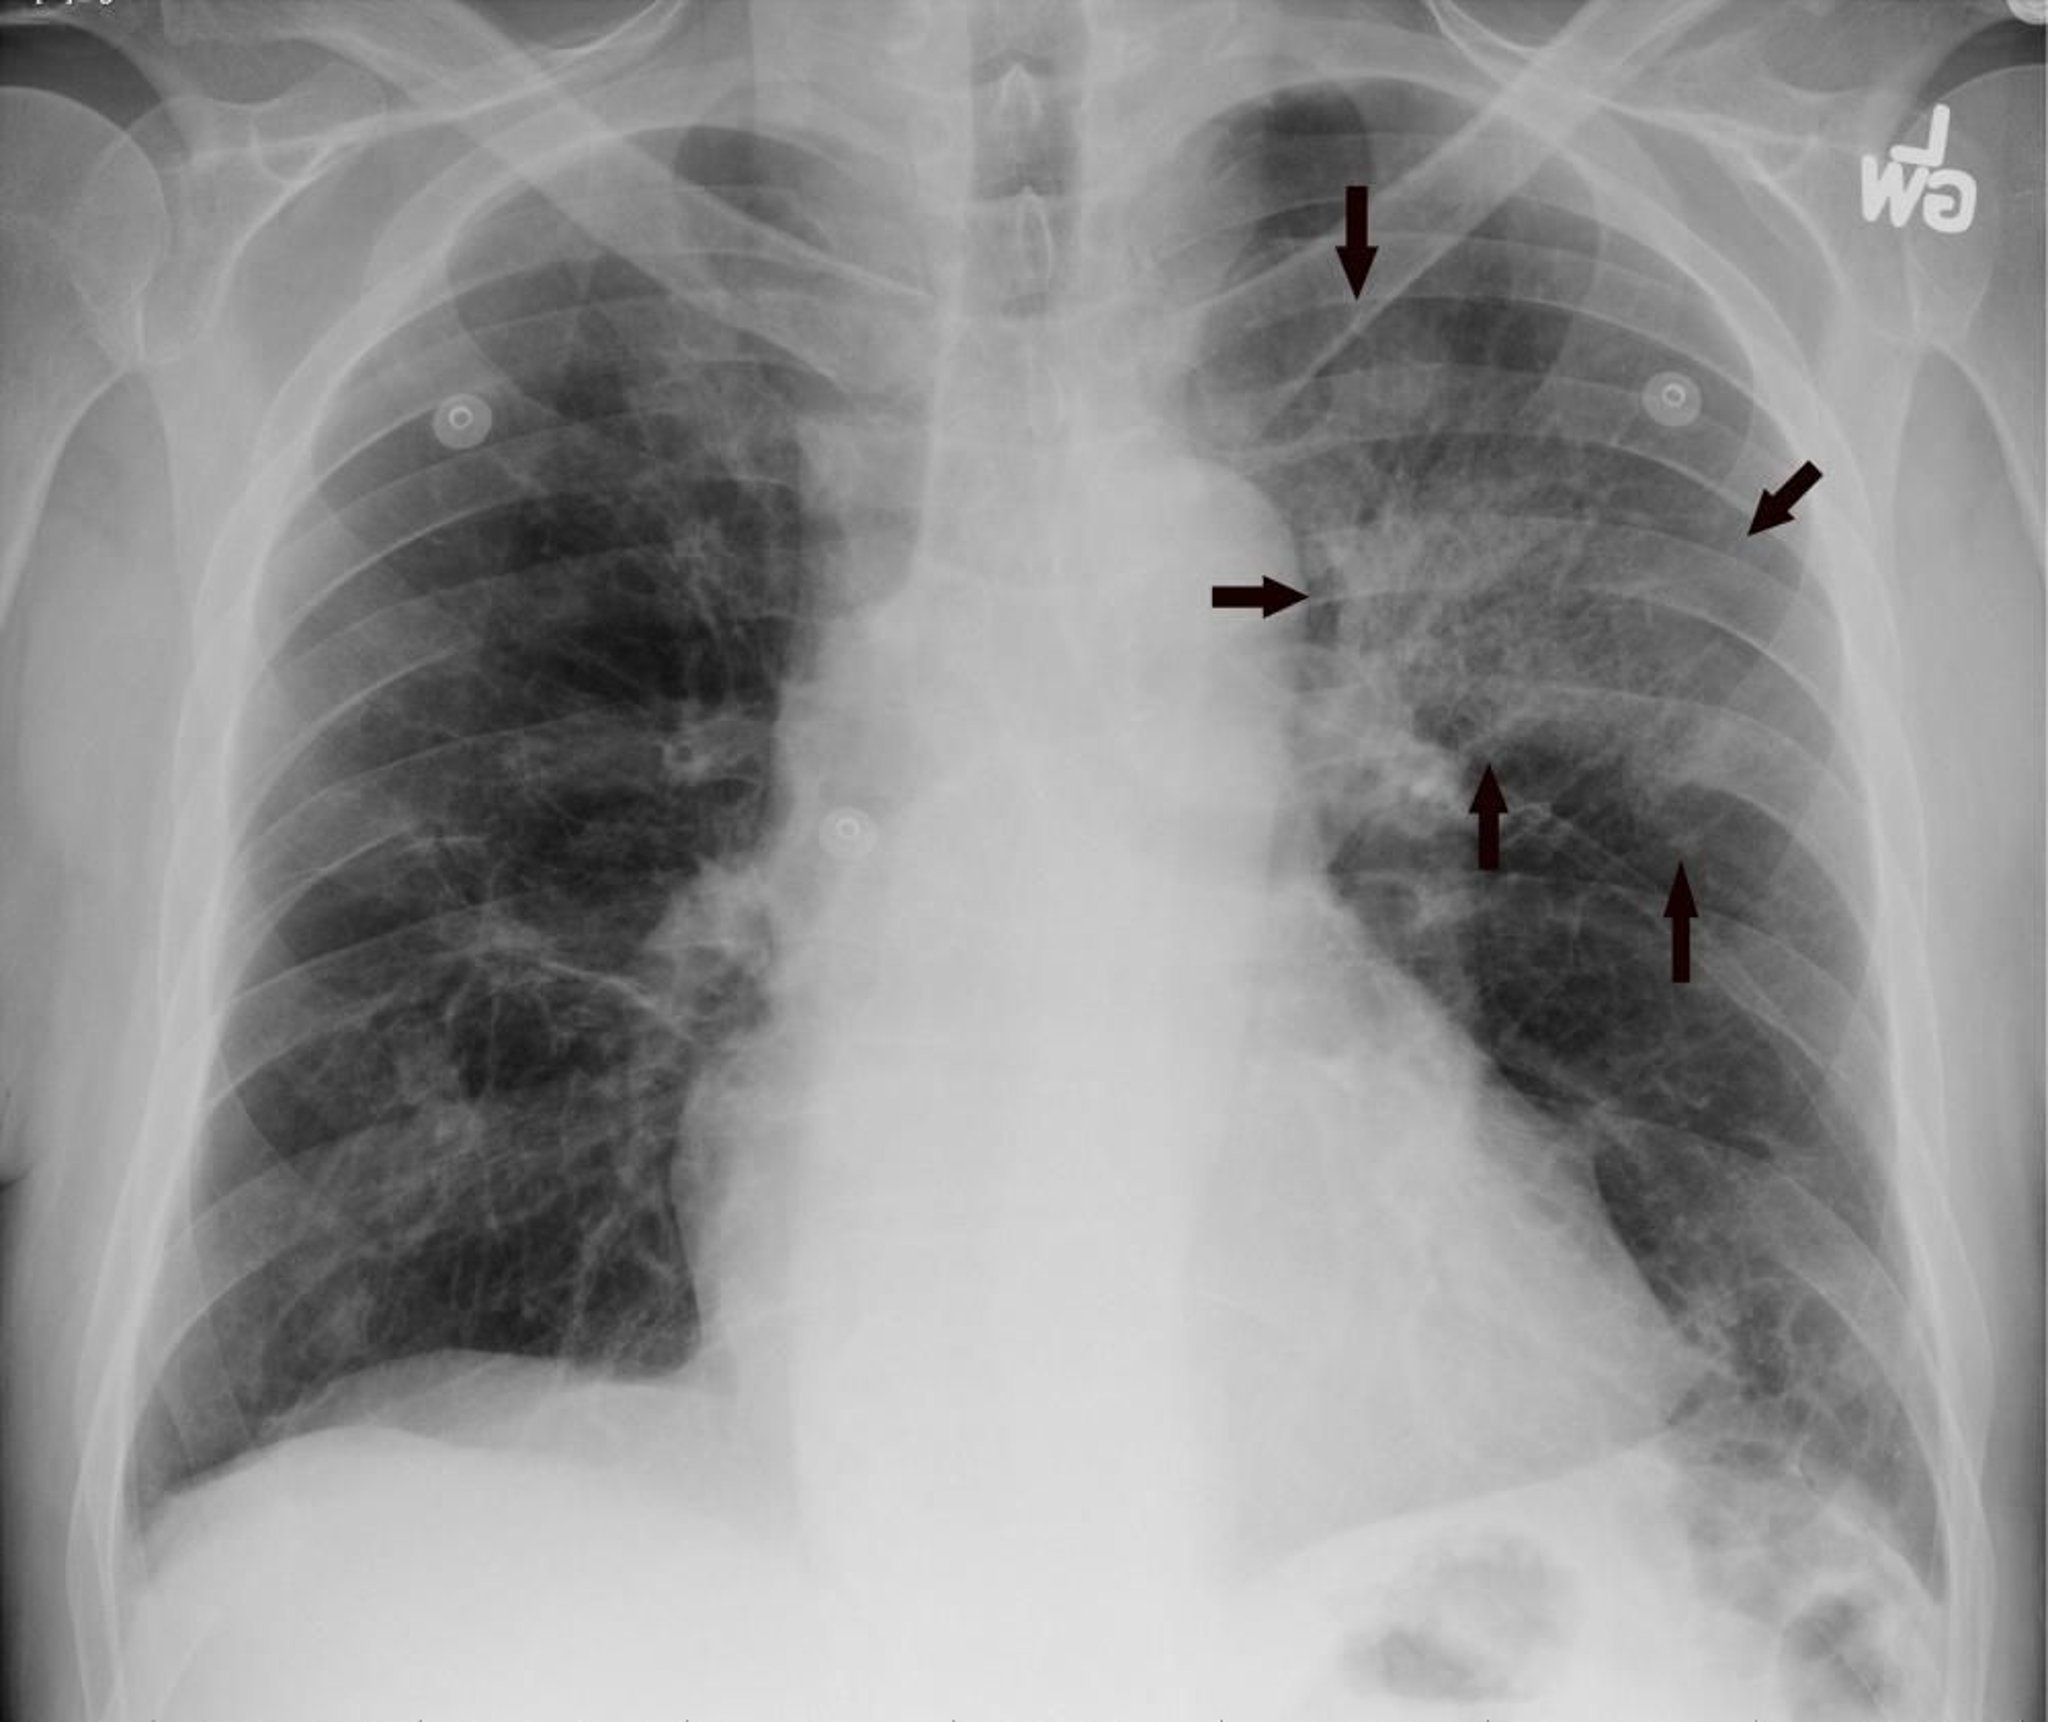

La radiografía de tórax posteroanterior muestra un infiltrado del lóbulo superior izquierdo compatible con neumonía (flechas).